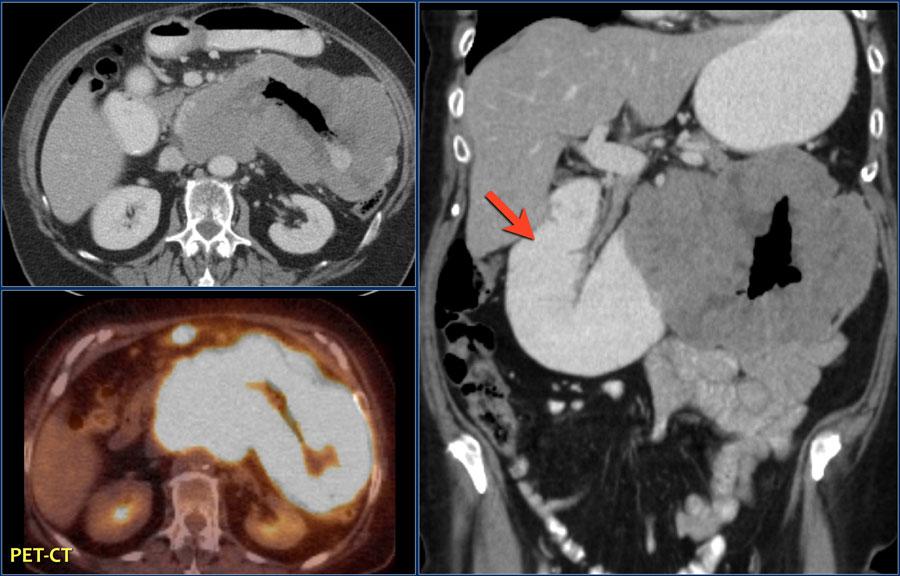

Виды роста злокачественных опухолей. Рост злокачественных новообразований. Злокачественные опухоли характеризуются. Форма злокачественной опухоли. ПЭТ кт онкология глиома. Метастазы в печени на ПЭТ кт.

ПЭТ кт онкология глиома. Метастазы в печени на ПЭТ кт. Лимфангиома брыжейки кт. Лимфома брыжейки тонкой кишки кт.

Глиома внутримозговая кт. Метастатические опухоли мозга. ПЭТ кт томограмма. Кт, ПЭТ И ПЭТ/кт. ПЭТ кт с контрастом. Скопление контраста ПЭТ кт.

ПЭТ кт томограмма. Кт, ПЭТ И ПЭТ/кт. ПЭТ кт с контрастом. Скопление контраста ПЭТ кт. Метастатическое поражение печени. Метастатические опухоли печени. Злокачественные образования печени.